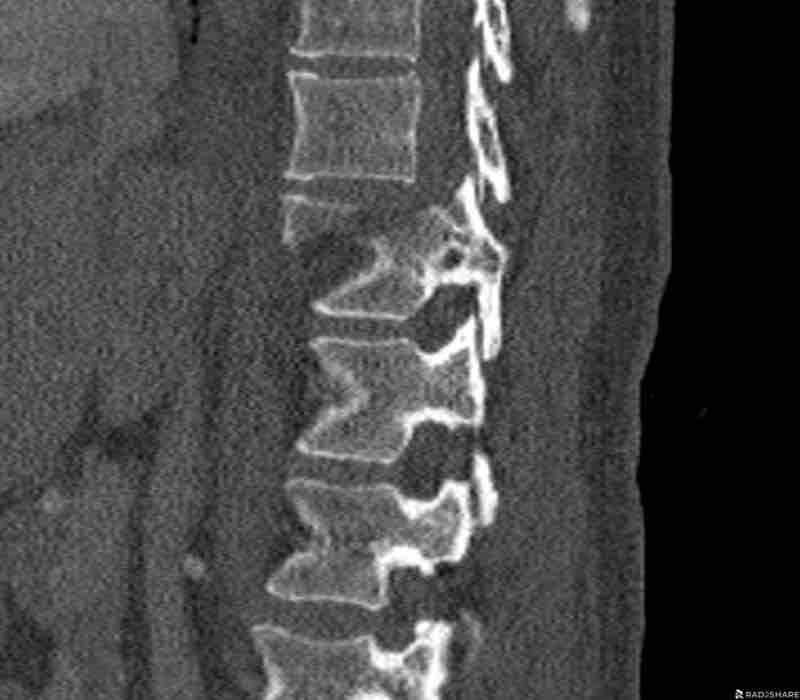

These images are of a 65 year-old woman who fell from her bike.

Scroll through the images.

What are the findings?

What is the highest AO-type of injury?

Findings

There is a type C injury.

In addition to the dislocation in the upper thoracic spine, there is also a sternum fracture, further increasing instability alongside the severe spinal injury.